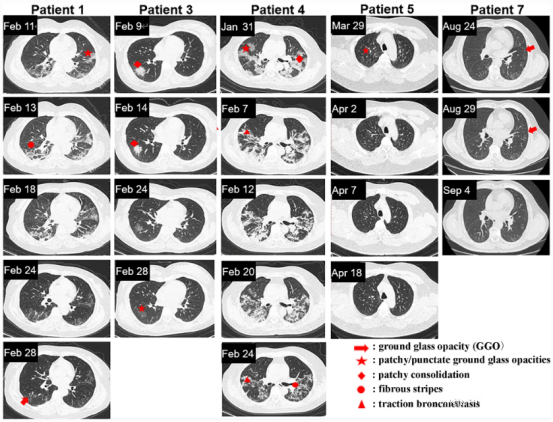

CT images of the other five patients, shown below, show a significant difference between the time it takes for lung lesions to be fully absorbed after a period of antiviral therapy (patients 1, 3, 4) and those who received exosome nebulization therapy from the beginning, and those who received exosome nebulization at the beginning recovered faster.

▲The recovery time of patients without exosome nebulization therapy is close to one month for 1, 3, and 4; Patients with exosome nebulization therapy had a recovery time of only about two weeks for 5 and 7.